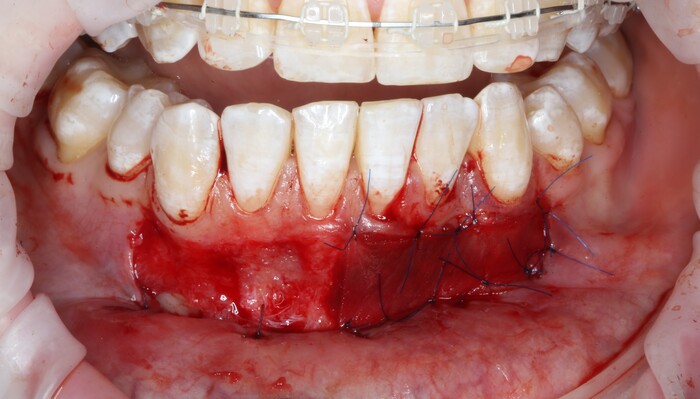

2 – проведение пластики десны.

Был взят трансплантат в области бугра верхней челюсти (это то место, где раньше был зуб мудрости).